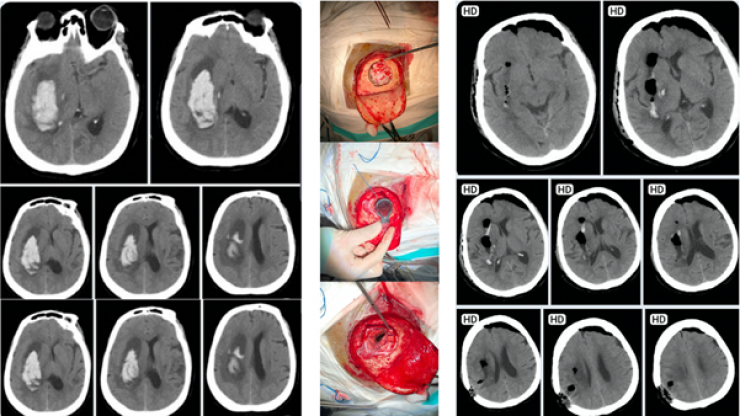

3. Cứu sống người bệnh bị xuất huyết não nặng bằng robot Modus V Synaptive tại Bệnh viện Nhân dân 115

Khối máu tụ lớn chèn ép não được robot Modus V Synaptive hỗ trợ lấy sạch, người bệnh phục hồi tốt sau 5 ngày điều trị tại Bệnh viện Nhân dân 115

Ngày 16/06/2019, Bệnh viện Nhân dân 115 tiếp nhận một người bệnh nữ, 62 tuổi với chẩn đoán xuất huyết não ngày 2, tăng huyết áp, nhập viện trong tình trạng lơ mơ, liệt nữa người trái. Lúc nhập viện người bệnh hôn mê, Glasgow 10 điểm (E=2, V=3, M=5), liệt ½ người trái, được tiến hành chụp CT sọ não ghi nhận xuất huyết não cấp tính tạo khối máu tụ bán cầu phải, chèn ép các cấu trục kế cận, tổn thương vỡ vào não thất bên bên phải làm tụ máu não thất bên bên phải, kèm thương tổn não cũ vùng nhân đậu trái. Bác sĩ chuyên khoa ngoại thần kinh quyết định phẫu thuật lấy máu tụ bằng phương pháp xâm lấn tối thiểu với sự hỗ trợ của robot Modus V Synaptive, sử dụng ống “brain path” để lấy khối máu tụ. Người bệnh được gây mê toàn thân, đặt tư thế đầu nghiêng trái nhẹ, rạch da thái dương – đính sau phải, đường thẳng 4cm, bộc lộ sọ, khoan mở sọ tối thiểu một lỗ 3cm đường kính vào cực dưới khối máu tụ. Qua hệ thống robot, mở màng cứng, đốt nhẹ vỏ não. Dùng drain path chọc dò theo hướng dẫn định vị đi vào cực dưới khối máu tụ. Máu tụ tự trào ra theo áp lực trong sọ và theo hướng trọng lực cao thấp, hạn chế hút máu tụ. Đánh giá lượng máu cục còn sót lại không đáng kể, cầm máu bằng keo Floseal. Hậu phẫu ngày 01: người bệnh còn thở qua nội khí quản, kết quả chụp CT sọ não sau mổ ngày 17/06/2019 ghi nhận khối máu tụ đã được lấy hết, cấu trúc đường giữa đã trả lại vị trí bình thường, khí trong sọ. Hậu phẫu ngày 2: người bệnh được rút ống nội khí quản, chuyển khoa Ngoại Thần kinh theo dõi. Hậu phẫu ngày 3,4: tri giác người bệnh cải thiện đáng kể, Glasgow 13 điểm (E=4, V= 4, M=5), còn yếu ½ người trái. Thở êm, vết mổ khô sạch, không sốt. Hậu phẫu ngày 5: Người bệnh ổn định, được chuyển bệnh viện Phục hồi chức năng điều trị tiếp.

Thông thường, theo phương pháp phẫu thuật cổ điển giải ép kèm lấy khối máu tụ, người bệnh phải trải qua ca phẫu thuật lớn thời gian mổ kéo dài, đường mổ lớn, mở nắp sọ rộng, xẻ vỏ não vuông góc với hướng đi của các bó dẫn truyền thần kinh, khi lấy máu tụ sẽ lẫn mô não lành, di chứng thần kinh không hồi phục, có thể gây ra các tổn thương mô não sau mổ, hậu phẫu nặng nề, nhiều tai biến, biến chứng sau mổ làm ảnh hưởng kết quả phẫu thuật. Phẫu thuật xuất huyết não bằng hệ thống robot Modus V Synaptive mang đến sự chính xác, hiệu quả hơn hẳn, kiểm soát tốt ổ máu tụ, giúp giảm thiểu rất nhiều các tổn thương não khi so sánh với phương pháp phẫu thuật cổ điển. Thời gian phẫu thuật rút ngắn đáng kể, giảm thiểu các biến chứng do gây mê. Giảm thời gian hồi sức sau mổ giúp hạn chế các biến chứng nặng như viêm phổi, nhiễm trùng tiểu, loét chèn ép, viêm tắc mạch chi, giảm chi phí điều trị. Đây là xu thế hiện nay hiện nay của các trung tâm phẫu thuật thần kinh hiện đại. Với hệ thống robot chuyên dụng này, BV Nhân dân 115 đang hình thành một trung tâm đột quỵ hoàn chỉnh đầu tiên trên cả nước.